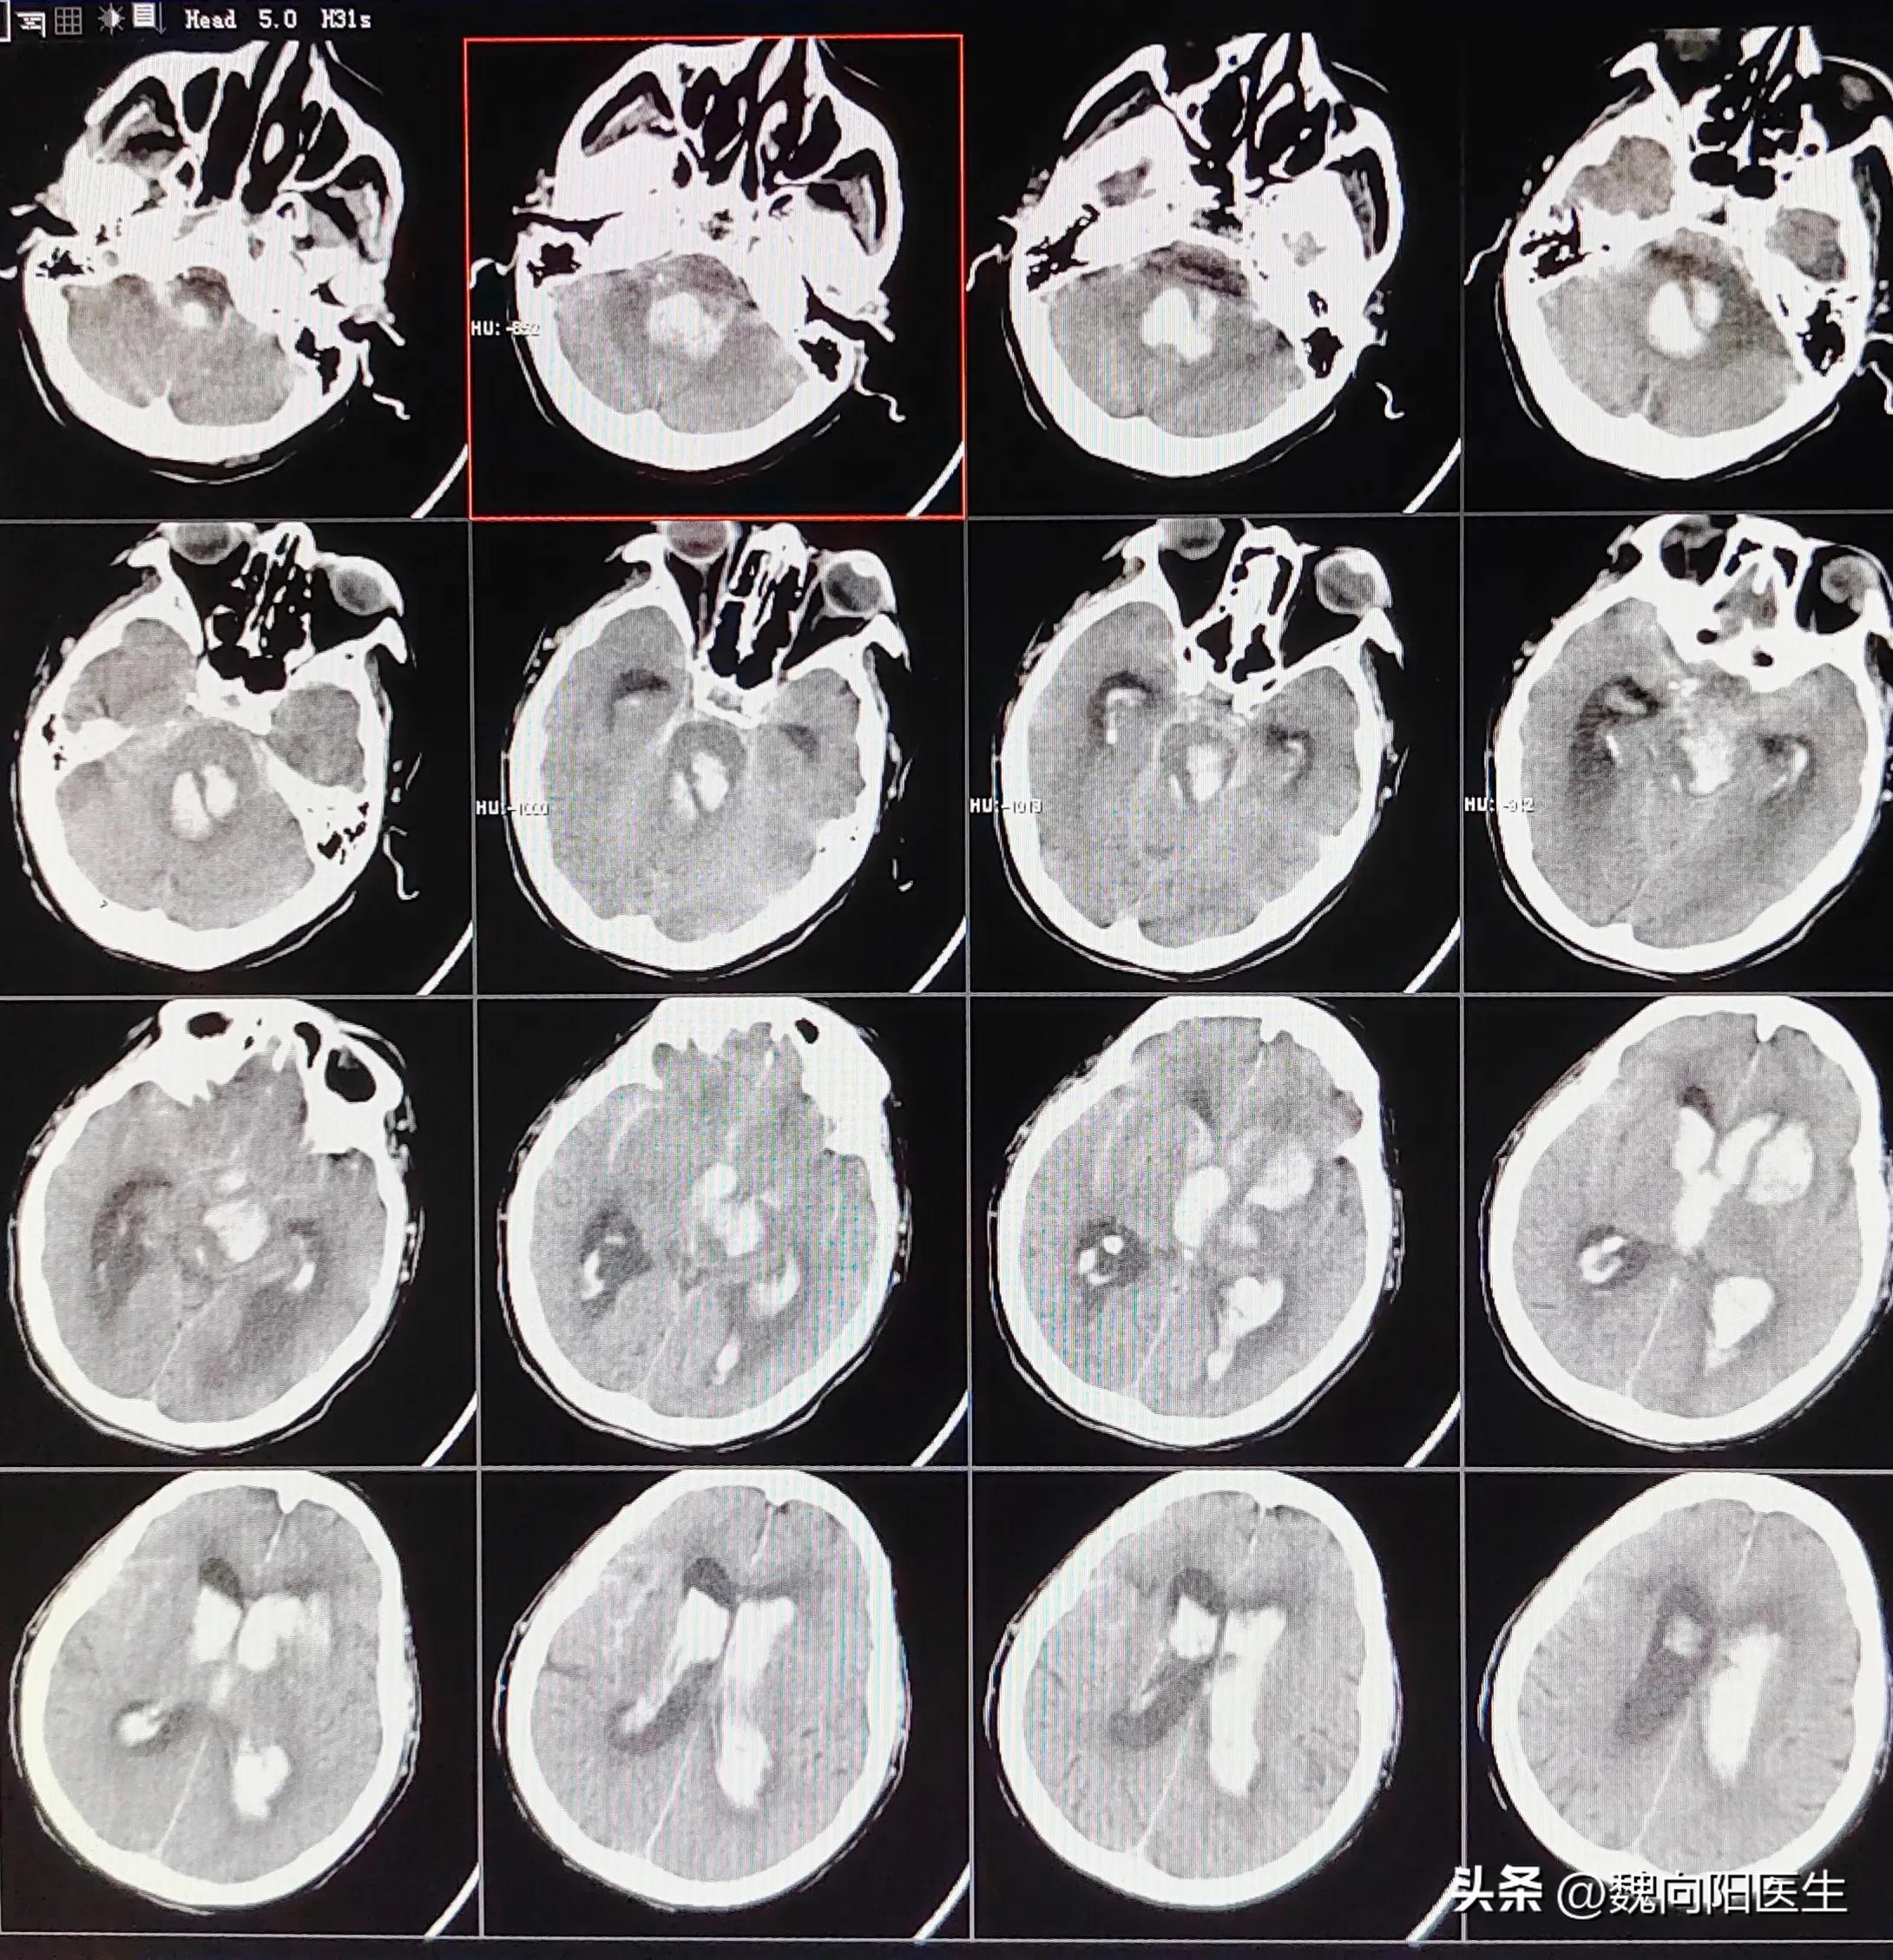

脑出血

脑出血患者